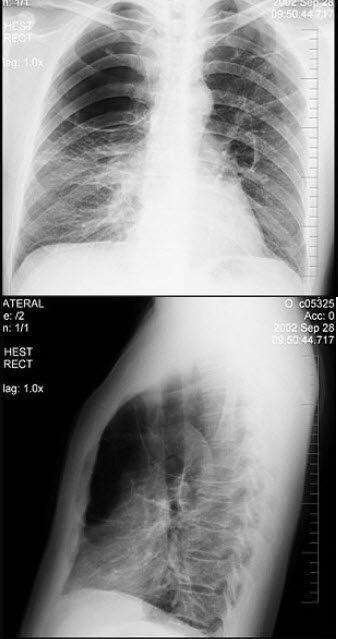

258、单项选择题

男性,62岁,常感胸闷、气逼,X线检查如图,最可能的诊断是()

A.右侧肺大疱

B.右侧气胸

C.右侧肺脓肿

D.右侧胸膜肥厚

E.右肺炎